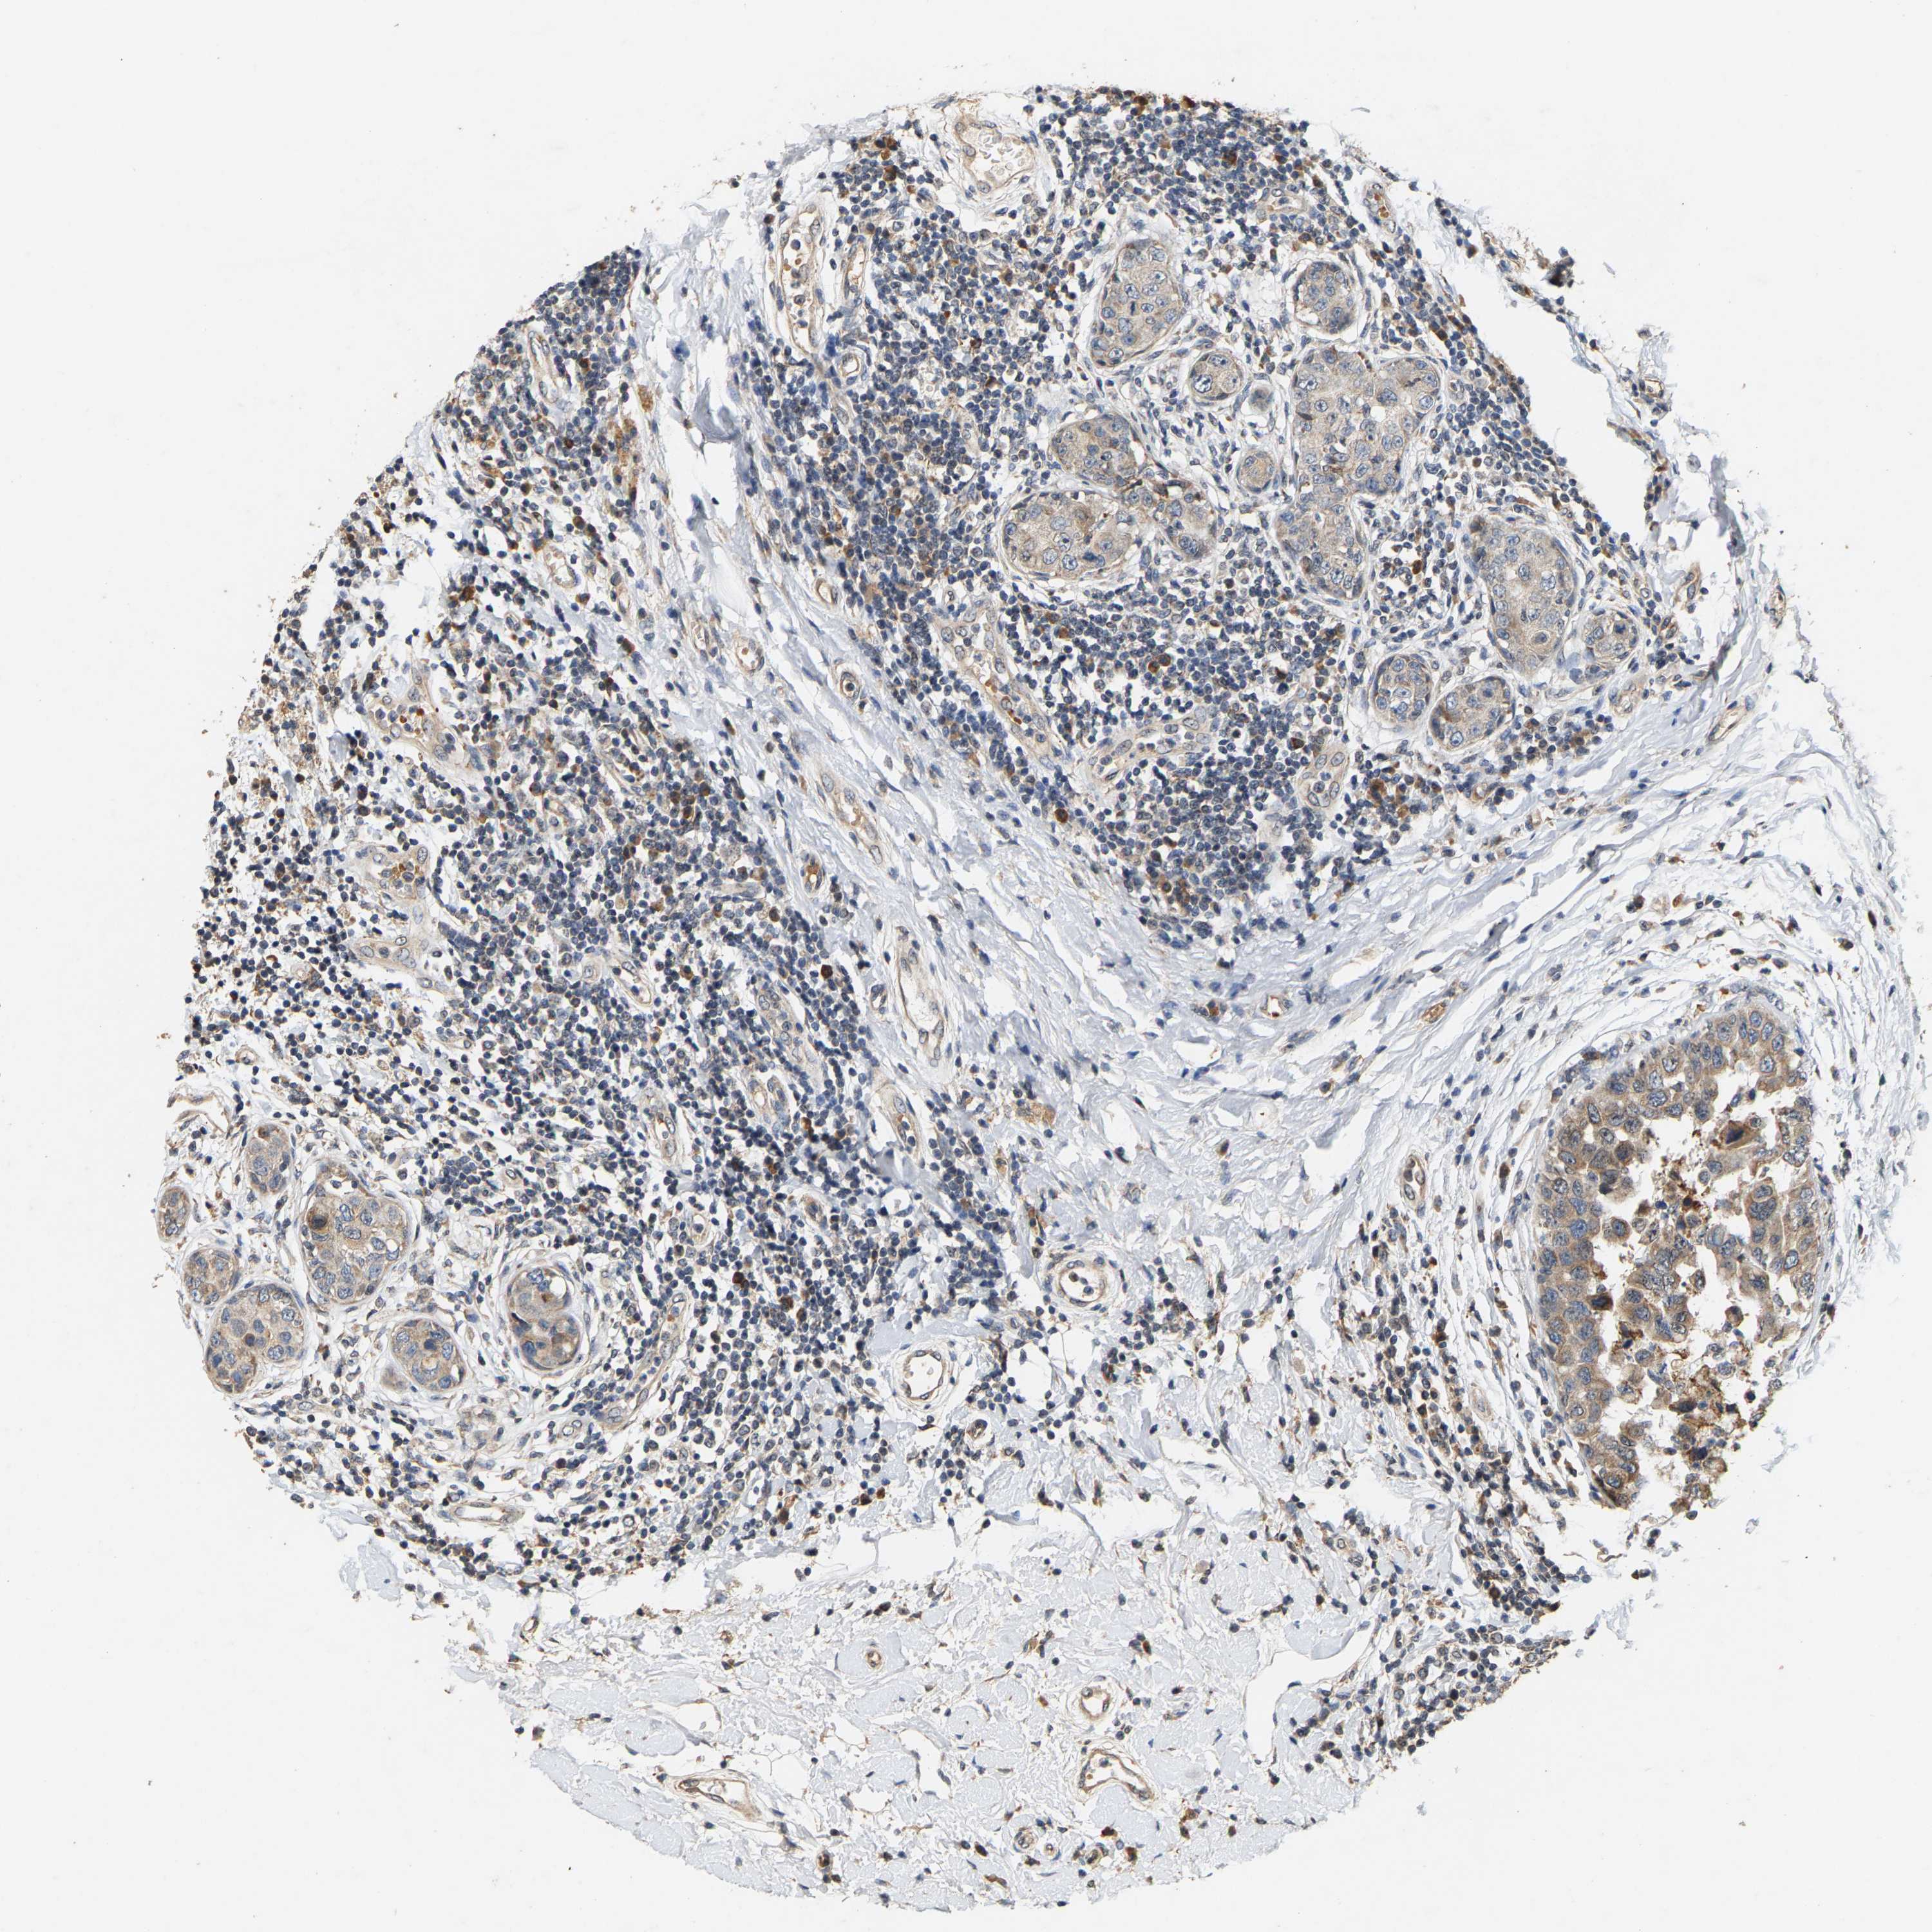

CANCER BREAST CANCER Show tissue menu

BRCA TCGA BRCA VALIDATION PROTEIN EXPRESSION